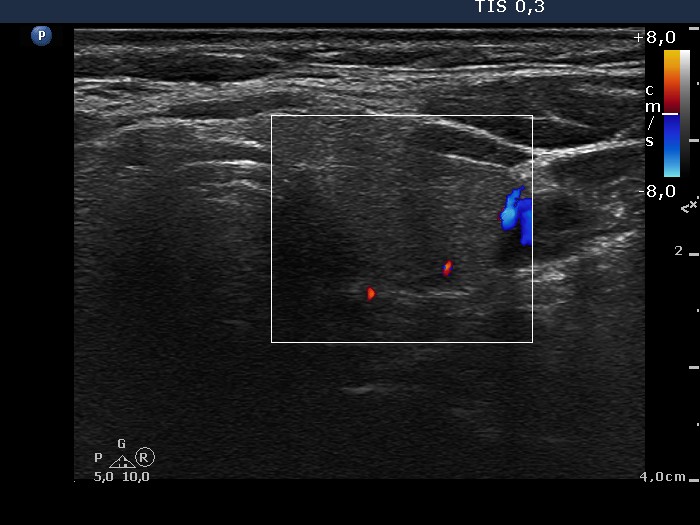

Benign nodular hyperplasia - Case 59. (ultrasonographic picture 9)

Left lobe, horizontal scan, color Doppler mode. The vascularization is not specific.